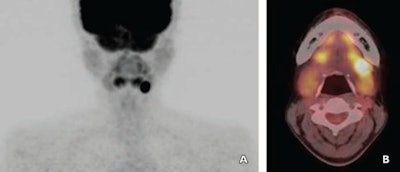

The researchers retrospectively evaluated 21 women and 18 men (mean age, 51.6 years) with salivary gland tumors who underwent FDG-PET/CT at the hospital between August 2007 and July 2011. They assessed a total of 40 salivary gland tumors (one patient had two tumors).

The patients fasted for at least four hours before receiving an injection of 3.7 MBq/kg of FDG. The early-phase set of PET/CT images (Aquiduo, Toshiba Medical Systems) of the head and neck from skull base to subclavicular area were acquired 60 minutes after injection. The scan protocol was repeated for delayed-phase imaging 120 minutes after FDG injection.